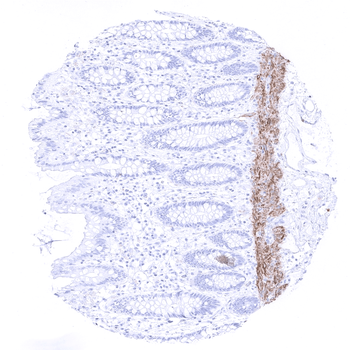

A moderate intensity Calponin 1 immunostaining is seen in the muscularis mucosae in a colon sample.